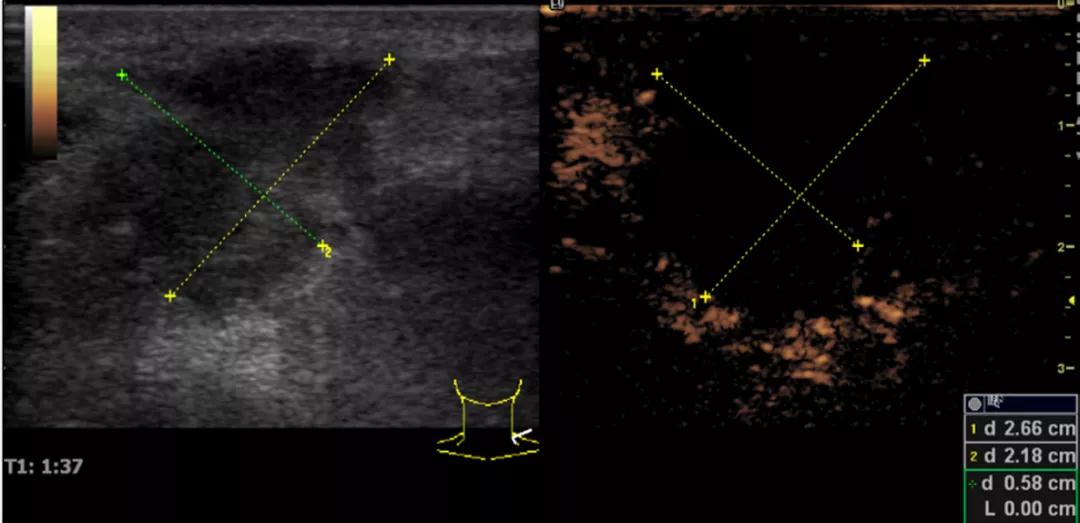

第5例是乳腺癌的患者,右乳恶性肿瘤术后化疗后1年出现淋巴结转移,患者基本情况差,拒绝放化疗,行局部热消融后也实现充盈缺损,术后一个月强化信号消失。

(病例5图例)